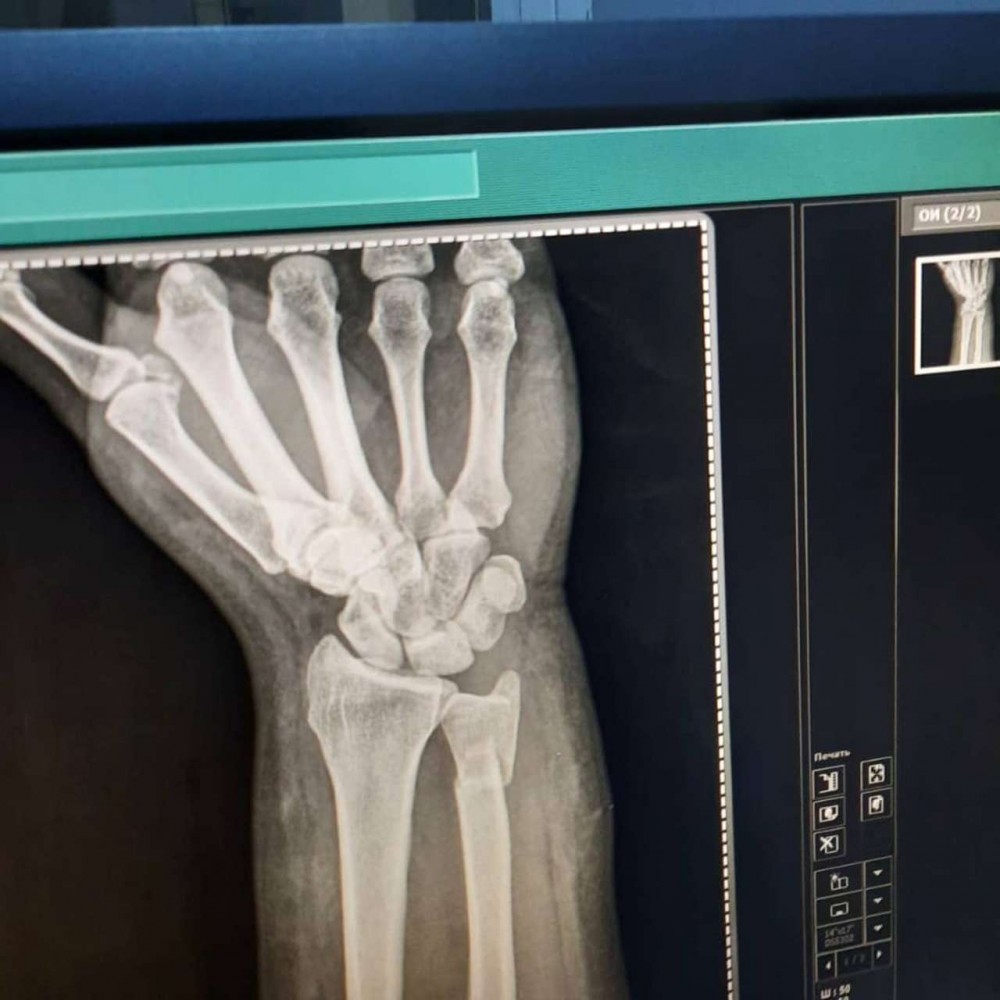

Azərbaycanlı aparıcının biləyi qırıldı - FOTOLAR

Tanınmış aparıcı Aytən Səfərovanın başına iş gəlib.

32gun.az xəbər verir ki, aparıcının bilək sümüyü sınıb. Bu barədə Səfərova instaqramda məlumat yayıb. O bildirib ki, bu günlərdə anası ağır əməliyyata hazırlaşır:

“Çox çalışdım ki, könlümü fərəh tutum, fikirləşdiyimi büruzə verməyim, özümü “sındırmayım”, lakin sümüyümü sındırdım. Həkimlər vaxtında müdaxilə etdilər.  Hələ ki, ağrıkəsicisiz mümkün deyil, amma biz güclü qadınıq. İnşallah bu da keçər. Özünüzü qoruyun”.